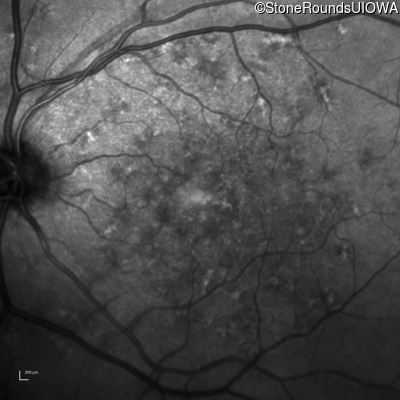

AR Stargardt Disease (IIA)

Age at visit: 59 years (Visit 3)

This 59 year old woman first noticed vision loss in her right eye a few months earlier. She has a cousin with Rhodopsin-associated RP.

Diagnosis & molecular findings

Disease Gene Allele 1 variant(s) Allele 2 variant(s) Inheritance mode

AR Stargardt Disease ABCA4 Arg219Thr AGA>ACA Gly863Ala (G)GA>(G)CA AR